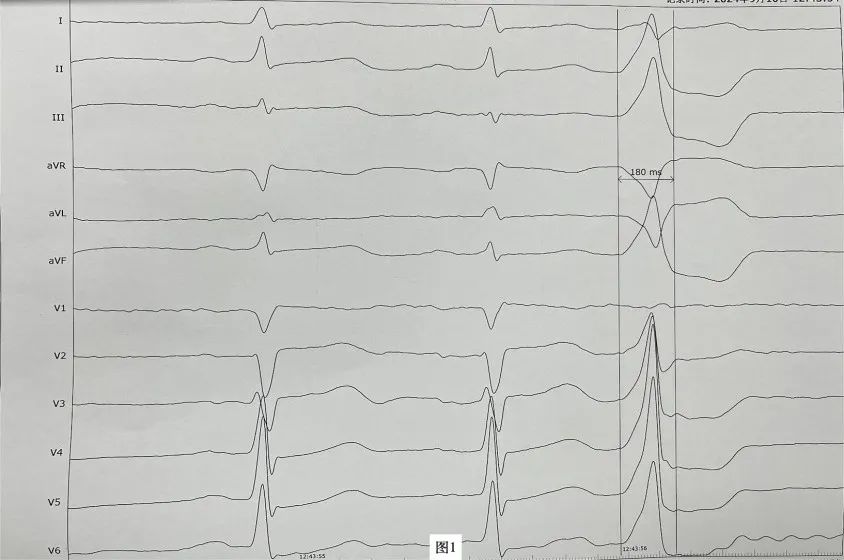

李先生(化名),近年来一直受病痛折磨,反复心悸、胸闷发作,夜间难以入睡,多次在外院就医治疗效果均不理想。近日,李先生再次因心悸症状明显慕名来到昆医大附二院心血管内科二病区周明礼门诊就诊。患者心电图检查提示有室性早搏,24小时动态心电图提示室早超过40000次,占总心跳40%左右。经诊断,患者有频发室性早搏,心悸症状因室早所致。周明礼认真分析病情后,告诉患者这个病不用开刀,在清醒状态下,从腿部穿刺血管将消融导管送入心脏进行心脏射频消融治疗就可以得到根治,并且术后第二天就可以下床走路。但因该患者早搏起源左室summit区域(图1),位置刁钻,难度较大,能够成功手术的医院屈指可数。昆医大附二院心血管内科二病区开展射频消融手术多年,该区域室性早搏消融成功率较高,受疾病困扰多年的患者听到这个消息很高兴,并表示辗转就医多年终于看到了希望,决定在医院进行手术治疗。